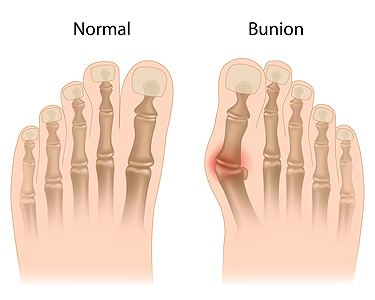

Bunions may appear in several ways, each with its own challenges. Some are mild and cause only slight irritation, while others are moderate and with them, the big toe is pushed inward. Severe bunions can create significant pain and limit daily activities. A bunionette, also known as a tailor’s bunion, forms on the outside of the foot near the little toe. Juvenile bunions often develop in younger people and are usually linked to inherited foot structure. Treatment options vary depending on how advanced the bunion is. Simple changes such as wearing wider shoes, applying padding, or using custom orthotics can relieve pressure. More serious bunions may require surgery to correct the alignment and ease discomfort. If you notice a bunion is starting to affect your comfort or mobility, it is suggested that you see a podiatrist who can provide the right diagnosis and treatment plan.

What Is a Bunion?

Bunions are painful bony bumps that usually develop on the inside of the foot at the joint of the big toe. As the deformity increases over time, it may become painful to walk and wear shoes. Women are more likely to exacerbate existing bunions since they often wear tight, narrow shoes that shift their toes together. Bunion pain can be relieved by wearing wider shoes with enough room for the toes.

Causes

- Genetics – some people inherit feet that are more prone to bunion development

- Inflammatory Conditions - rheumatoid arthritis and polio may cause bunion development

Symptoms

- Redness and inflammation

- Pain and tenderness

- Callus or corns on the bump

- Restricted motion in the big toe

In order to diagnose your bunion, your podiatrist may ask about your medical history, symptoms, and general health. Your doctor might also order an x-ray to take a closer look at your feet. Nonsurgical treatment options include orthotics, padding, icing, changes in footwear, and medication. If nonsurgical treatments don’t alleviate your bunion pain, surgery may be necessary.